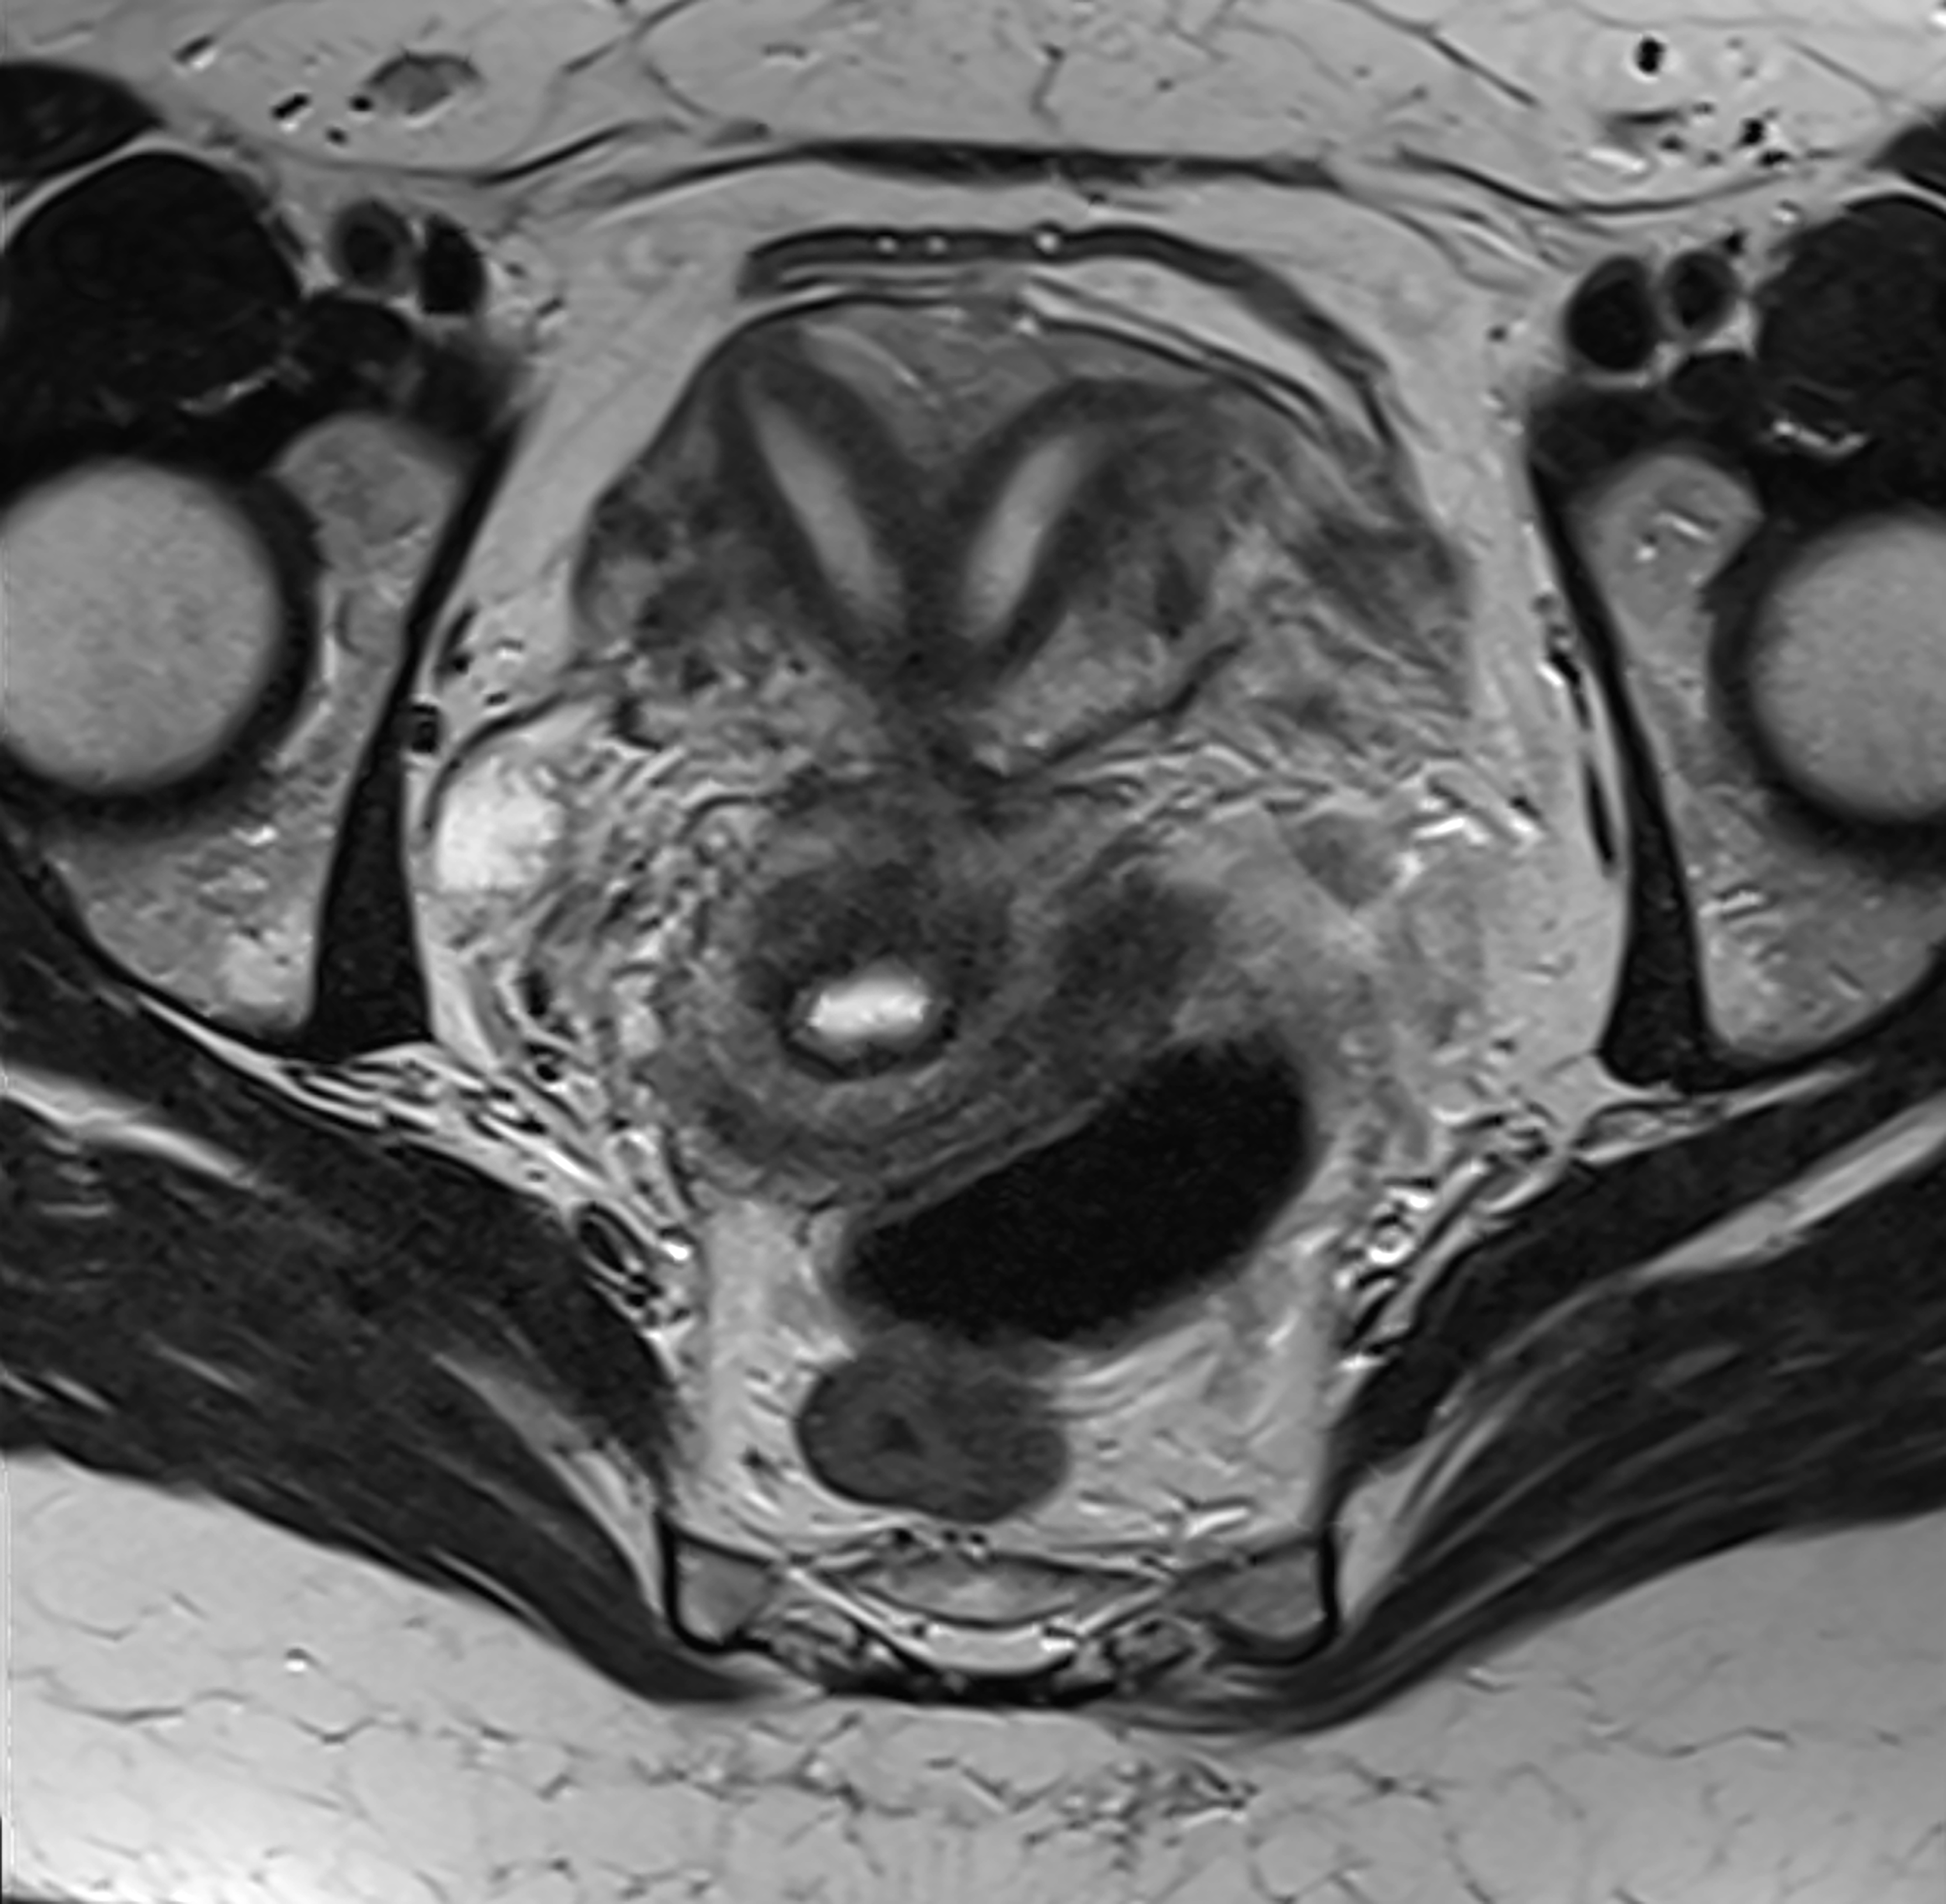

11.“Apparently we know next to nothing about fibroids, which like 75% of women have at some point in their lives. That’s great, considering that the largest one ever removed was 100 pounds, so not exactly a minor issue.”

16.“We don’t know what causes endometriosis or how to treat it effectively. The leading theory is ‘retrograde menstruation,’ which occurs in 80-90% of women. OK…so why do 80-90% of women not have endometriosis?”